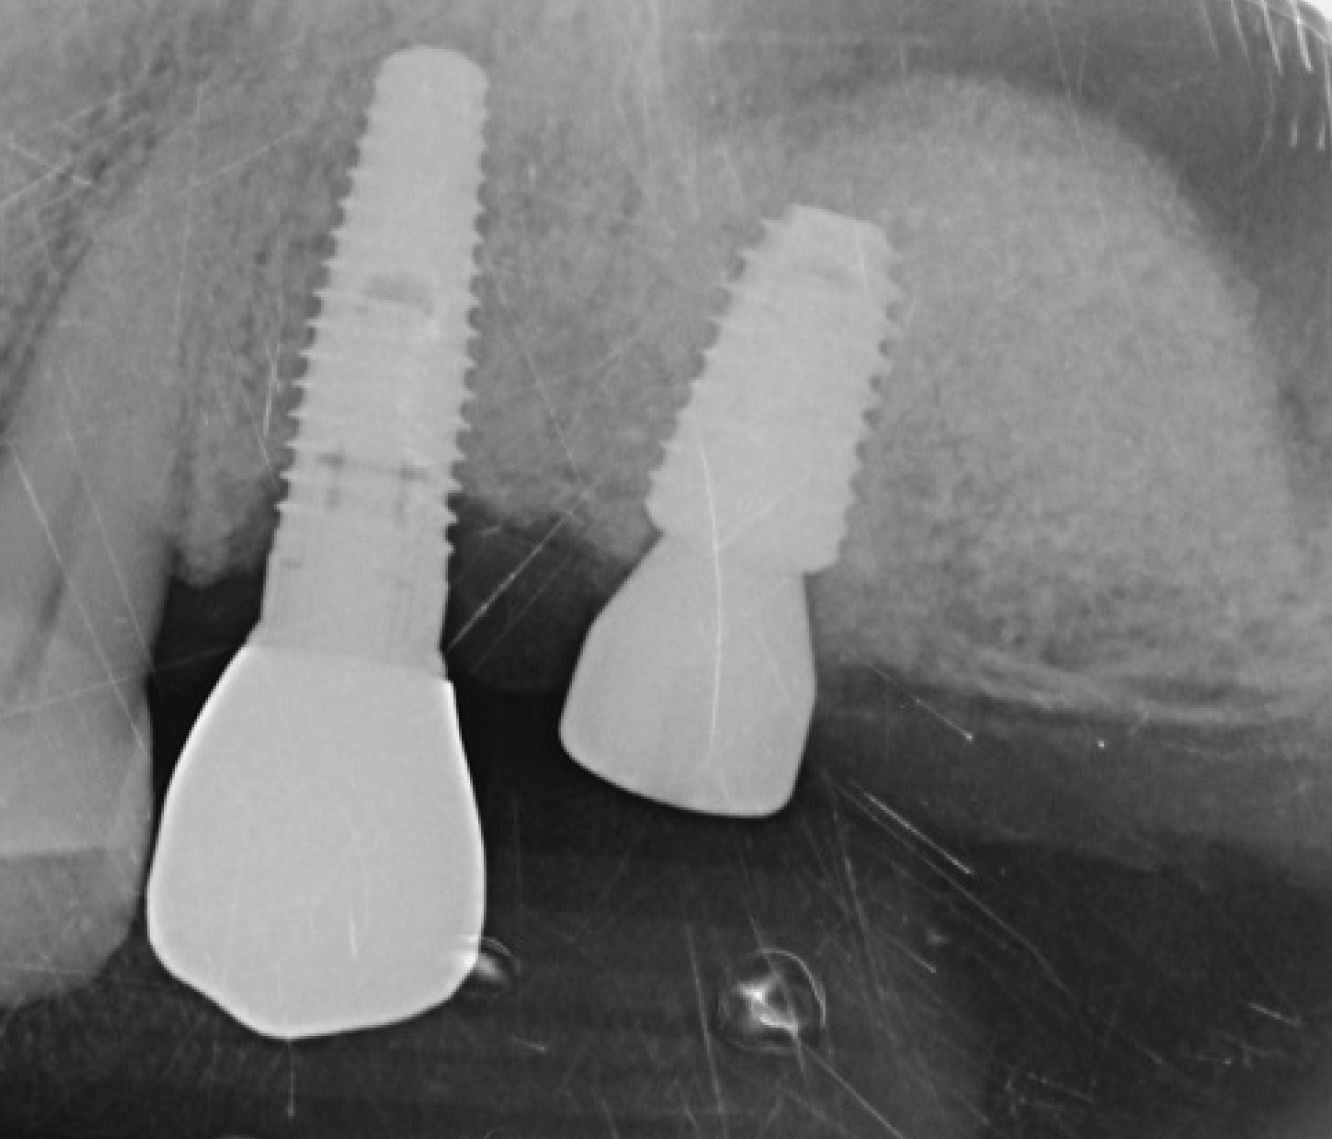

Director’s Clinical Cases

Director’s Clinical Cases